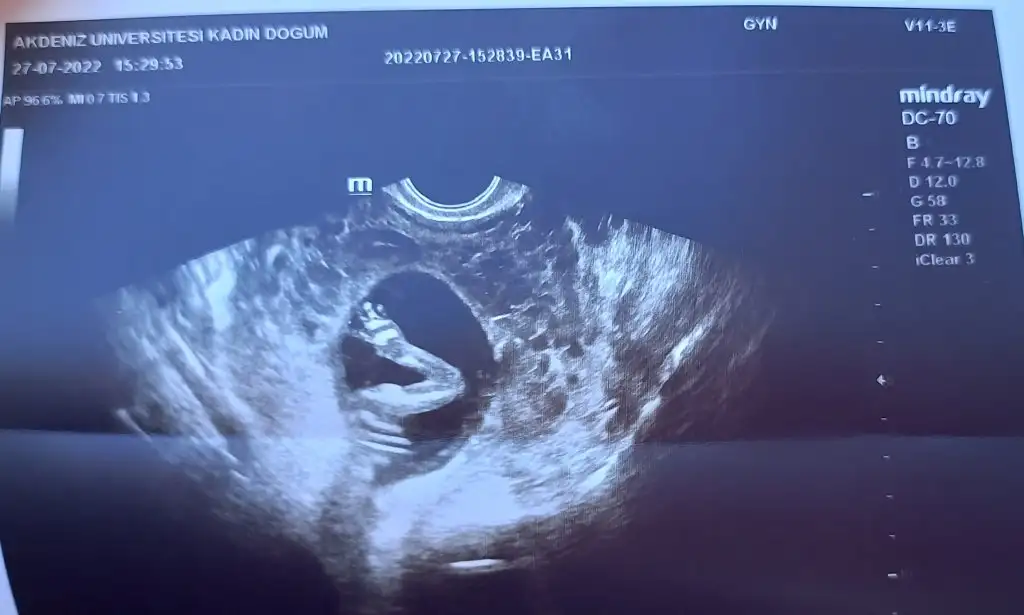

İnsan içinde böyle bir mucize taşıdığına inanamiyorDün doktor yakaladı![]()